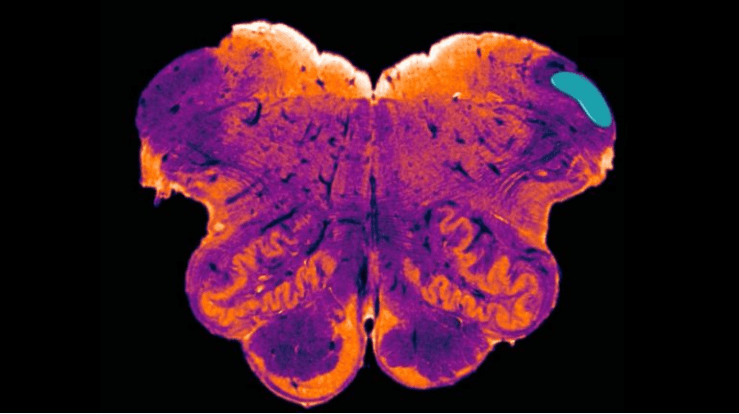

Dicha región ha sido bautizada con el nombre de núcleo endorestiforme (endorestiform nucleus), y se encuentra situada dentro del llamado cuerpo restiforme, en la base del cerebro, muy cerca de donde se une a la médula espinal.

La confirmación la obtuvo mientras tomaba imágenes para un nuevo atlas del cerebro, usando una novedosa técnica de coloreado de las células cerebrales, que permite clasificarlas en base a su función y a los neurotransmisores que producen, y no por su forma o apariencia.

Fue así como encontró al conjunto de células que forman el núcleo endorestiforme. “Fue como encontrar una isla en medio de un río”, explicó.